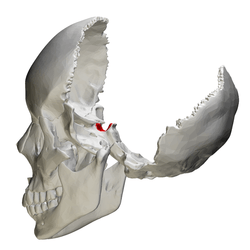

Human skull seen from side (parietal bones and temporal bones have been removed). Sella turcica shown in red. | |

Human skull seen from side (parietal bones and temporal bones have been removed). Sella turcica shown in red.

Human skull seen from side (parietal bones and temporal bones have been removed). Sella turcica shown in red. Hypophysial fossa shown in red.